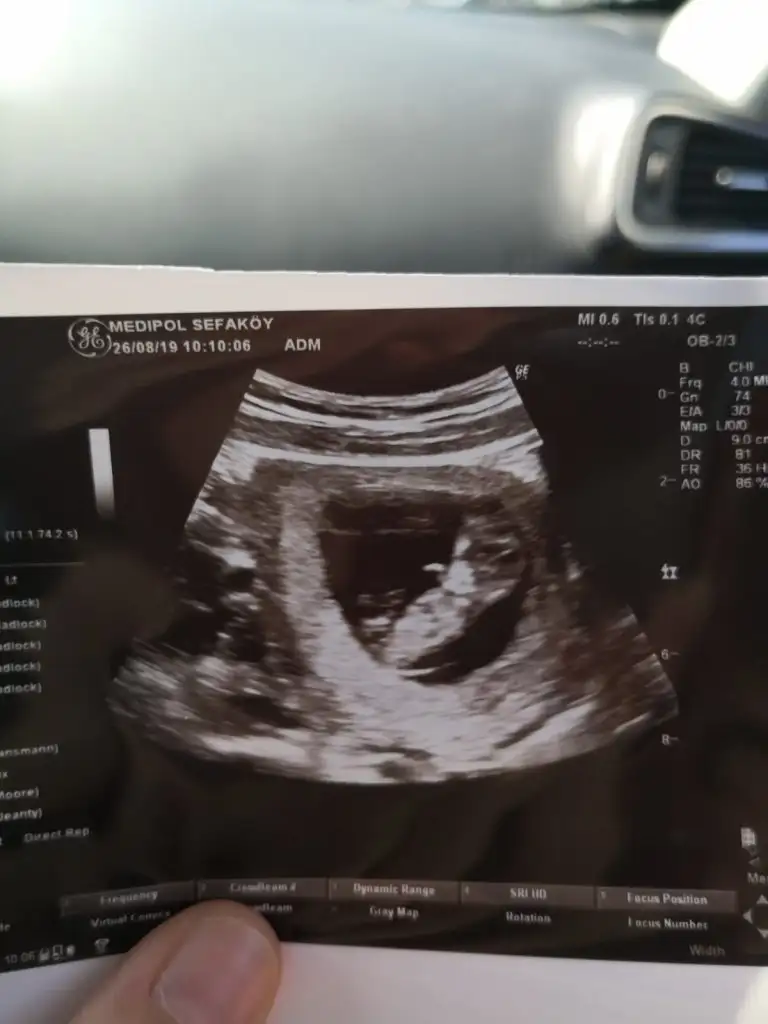

ErkekEki Görüntüle 2301494 Eki Görüntüle 2301495 Merhaba bende tahmin alabilirmiyim

ErkekSelam kızlar. 10+5 günlük hamileyim, var mı bi tahminleriniz

Net olmamakla birlikte kız başka usg varsa paylaşın

Bunda hic belli değil bence ama birde bu var :) yinede tesekkur ederimNet olmamakla birlikte kız başka usg varsa paylaşın

KızBunda hic belli değil bence ama birde bu var :) yinede tesekkur ederim